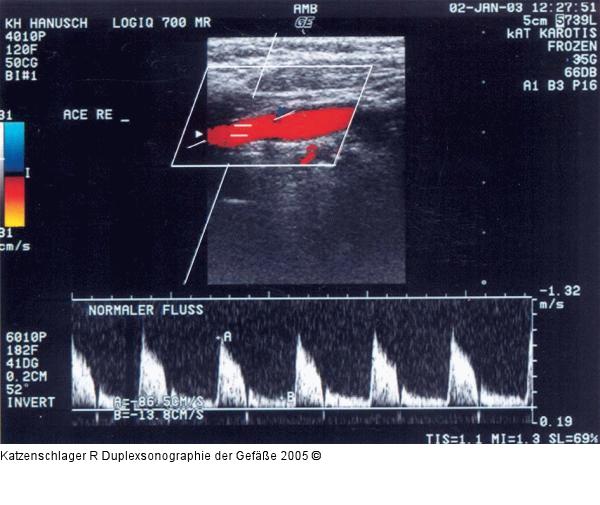

Abbildung 4a: Duplexsonographie - Karotis

Normalbefund der A. carotis externa |